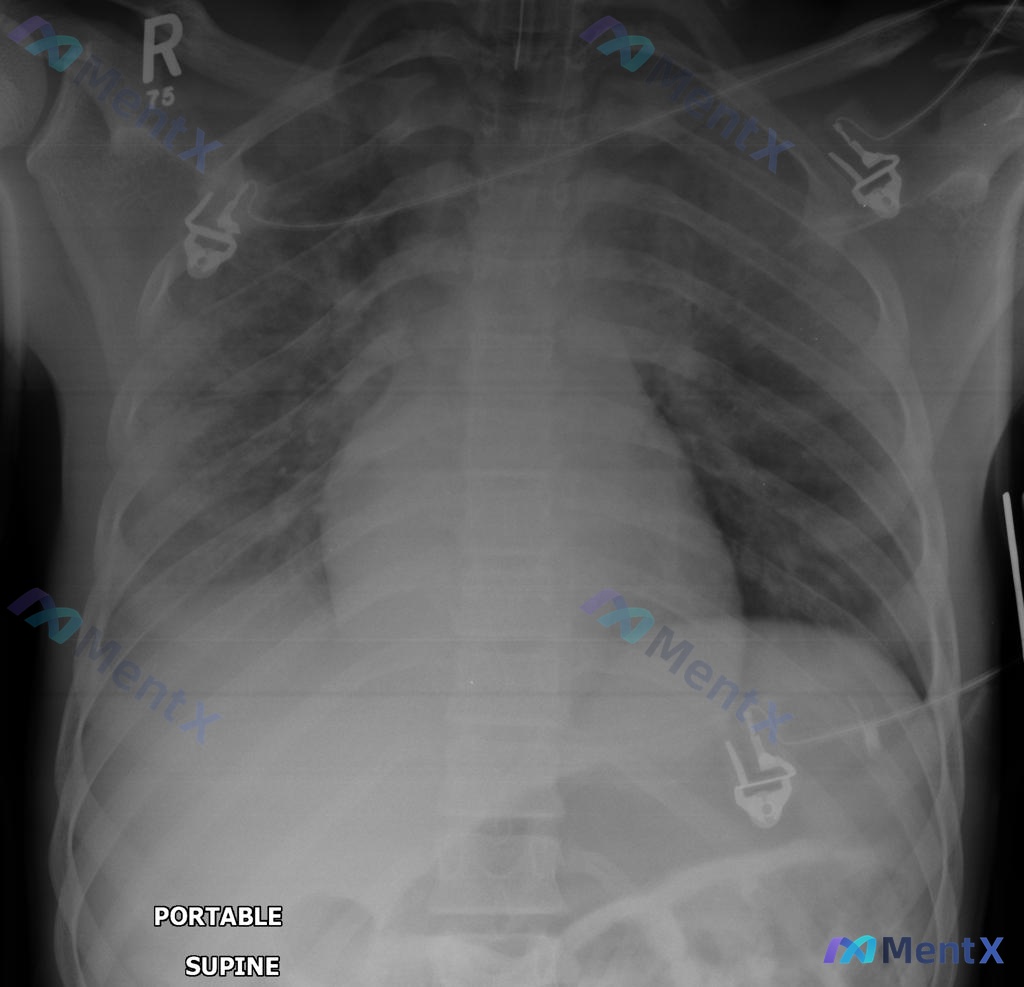

整理了一份值得讨论的病例: 62岁男性,因结肠肿块行左半结肠切除术,术后2天出现呼吸急促。目前体征: - 体温38.1°C,脉搏80次/分,呼吸22次/分,血压120/78mmHg - 室内空气SpO2 88%,双肺基部呼吸音、语颤均减弱 - 血气:pH 7.35,PaO2 70mmHg,PaCO2...